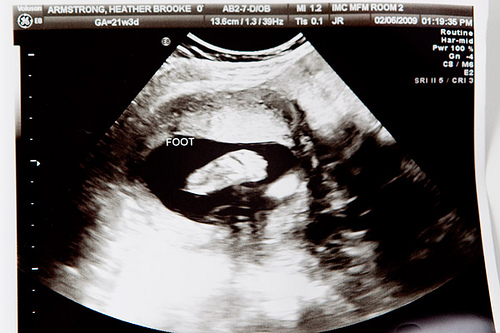

When we went in for an ultrasound a little over three weeks ago the doctor determined that I had a low-lying placenta, meaning it had formed at the lower half of the uterus. Excuse me while I slip into technical pregnancy talk for a moment: this can potentially be a problem if it doesn’t eventually move upward during the pregnancy because it can cover all or part of the cervix, a condition known as placenta previa that can cause bleeding or symptoms of early labor. She also couldn’t get the baby into a position that made it possible to inspect the end of her spine, so we scheduled another ultrasound to take a look at these concerns. That appointment was last Friday, and during that exam we got to meet the baby’s feet:

She yawned four times while we were watching, a gesture that silenced both me and Jon. I’ve only recently been able to feel her kicking around in the womb, so in many ways the only physical manifestation of the pregnancy so far has been my increasingly immobile body. This baby moves much differently than Leta did, and where Leta’s movements within felt like she was knocking down walls, this baby feels much more like she’s tiptoeing through the room. Watching her stretch her mouth wide open crystallized the reality of all these symptoms— the swollen fingers and toes, the flesh-eating acne, the embarrassing, uncontrollable flatulence that I often try to pass off as a creaky wooden floorboard. There is a certain look I have perfected when out in public, and when Jon turns around suddenly because he cannot believe that my dignity would allow such a sound to happen, all I have to do is raise my right eyebrow. This is code for YOU DID NOT HEAR ANYTHING.

Friday it sort of hit us squarely in the face: holy shit, there’s a human in there.

The placenta had moved upward significantly, and all the baby’s parts looked well-formed and jutted into and out of all the right places. The doctor asked us if we had chosen a name yet, and my answer was probably a lot more detailed than she had planned for. Thing is, we had a name picked out for a boy. In fact, we’ve had a name picked out for a boy since the beginning of our relationship. A boy was always going to be named after Jon’s grandfather, Truman, and then we’d only have to negotiate the middle name. Something short, precise, something I could yell easily and derisively when I discovered he had peed on the toilet seat.